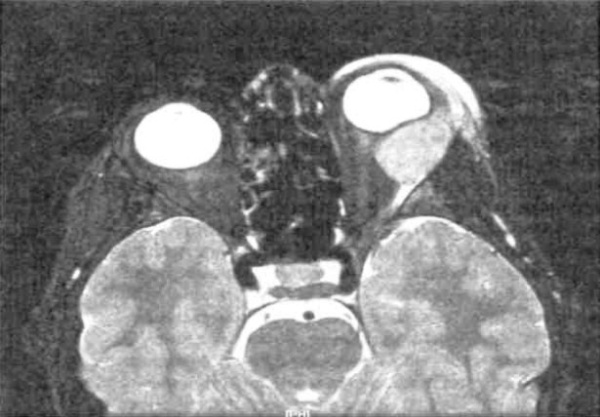

Ватоподобное желто-белое геморрагическое образование сетчатки и стекловидного тела, прилегающее к диску зрительного нерва у пациента 20 лет с бластным кризом хронического миелогенного лейкоза. Острота зрения снижена до движения руки. При МРТ диагностировано поражение глазницы и головного мозга (предоставлено Franco М. Recchia, MD). Вид образования, показанного на рисунке выше, пять недель спустя после облучения глаза и головного мозга и химиотерапии: наблюдается выраженный регресс образования. Острота зрения составляла счет пальцев (предоставлено Franco М. Recchia, MD). Атипичный отек диска зрительного нерва у мальчика восьми лет; острота зрения пораженного левого глаза 20/20. На тот момент пациенту была проведена химиотерапия по поводу системного рецидива ранее диагностированного лейкоза. Тот же глаз три месяца спустя. У пациента быстро развилась слепота. После лучевой терапии зрение не восстановилось, вскоре ребенок умер. Макропрепарат глазного яблока, полученный при вскрытии. Обратите внимание на геморрагический отек диска зрительного нерва и окружающих тканей. Микропрепарат пораженной сетчатки: определяется внутрисосудистая и экстравазальная инфильтрация лейкемическими бластными клетками (гематоксилин-эозин, х200).